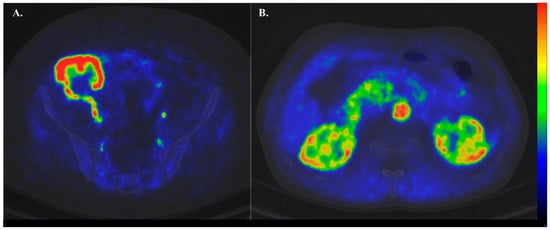

1.4. Basics of PET and Renal Cortical Perfusion

1.5. Tracers in Renal Perfusion PET

1.6. Clinical Settings Where Renal Perfusion Has Been Assessed with PET

- Kudomi, N.; Koivuviita, N.; Liukko, K.E.; Oikonen, V.J.; Tolvanen, T.; Iida, H.; Tertti, R.; Metsärinne, K.; Iozzo, P.; Nuutila, P. Parametric Renal Blood Flow Imaging Using [15O]H2O and PET. Eur. J. Nucl. Med. Mol. Imaging 2009, 36, 683–691. [Google Scholar] [CrossRef]